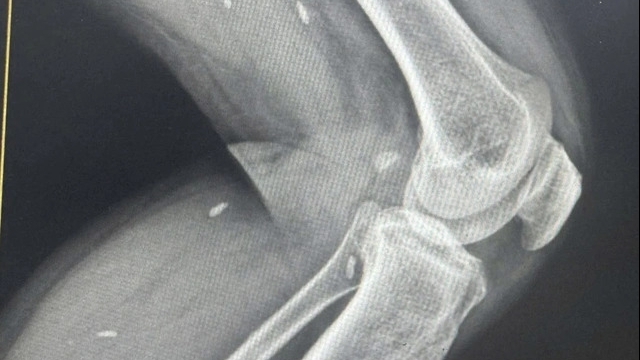

| Liên quan đến bệnh nhân 714, chiều 5/8 UBND quận Bắc Từ Liêm sơ bộ xác nhận có 18 người là F1 trên địa bàn quận, hơn 50 người là F2 và chắc chắn số lượng sẽ tiếp tục tăng lên. Các trường hợp này sẽ đưa đi cách ly ngay ở Trường Cao đẳng công nghệ cao Hà Nội. Bệnh viện Đa Khoa Hà Đông cho biết, bệnh nhân vào khám ở bệnh viện lúc 8h ngày 4/8, là bệnh nhân thứ 10 của phòng khám. Tại phòng khám sàng lọc về dịch tễ, bệnh nhân khai đi Đà Nẵng từ 4 - 7/7, đến 9/7 bệnh nhân có biểu hiện sốt ho. Đến ngày 3/8 bệnh nhân có đi khám ở Bệnh viện y học cổ truyền Bộ Công an, tại đây được chụp X quang và test nhanh COVID-19. Bệnh nhân tỉnh táo, không sốt, không có biểu hiện khó thở, kiểm tra test nhanh thì âm tính, chụp phổi trái thấy có một nốt mờ. Trước khi biểu hiện như vậy các bác sĩ đã yêu cầu bệnh nhân vào viện để điều trị. Tuy nhiên bệnh nhân có nguyện vọng đi khám về chuyên khoa hô hấp ở bệnh viện Trung ương. Chiều 5/8, sau khi biết tin bệnh nhân có kết quả khám xét nghiệm PCR dương tính thì bệnh viện đã báo cáo Sở Y tế, CDC, TTYT quận Hà Đông và đã tiến hành điều tra dịch tễ. Kết quả ban đầu có 3 nhân viên của bệnh viện, đó có 1 bác sĩ và 2 điều dưỡng có tiếp xúc với bệnh nhân. Trong quá trình làm việc cả 3 nhân viên này đều được trang bị phương tiên phòng hộ đảm bảo theo yêu cầu, bệnh viên đã phun khử khuẩn toàn bộ khu vực và các vị trí có liên quan. |